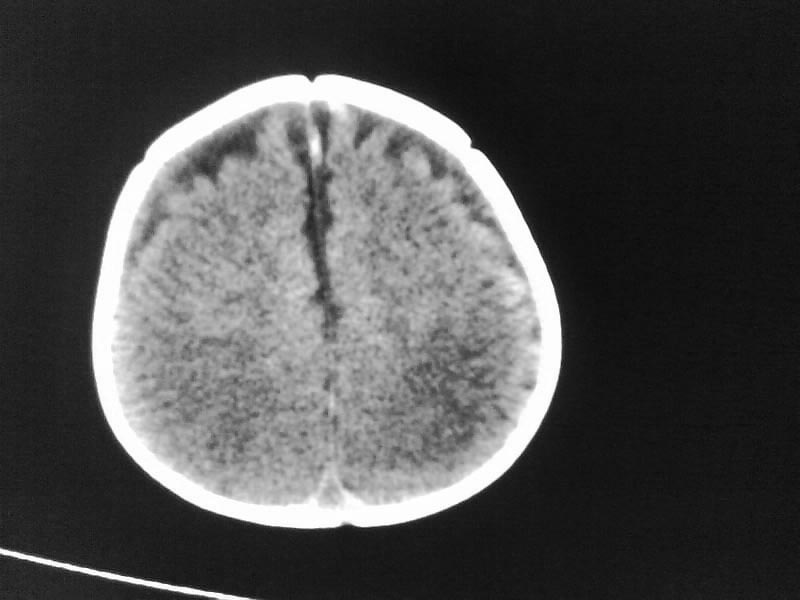

以下是引用随光逐影在2009-4-15 17:59:00的发言:[br]1)右侧额颞顶部硬膜下血肿。2)外部性脑积水。